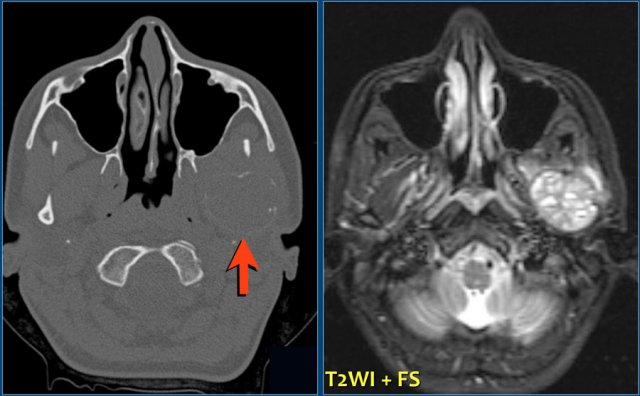

On the left a massive chondrosarcoma of the skull base with extension to the nasal and paranasal cavities and orbita.

CT demonstrates irregular calcifications produced by the tumor.

A T1-weighted image after Gd shows typical septal and nodular enhancement.